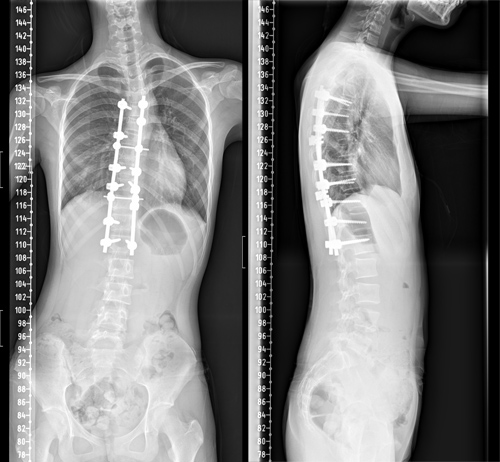

骨三科脊柱外科医护团队与麻醉科、手术室等进行了充分的术前讨论,制定周密的麻醉及手术方案。由朱述浪主任主刀,黄波副主任医师及汪智文医师共同为患者实施了后路脊柱侧弯矫形+胸廓成型手术,手术当中采用间接去旋转+多节段Ponte截骨松解技术。为了减少异体血的输入,术中采用了自体血回输,还使用了神经电生理监测为手术保驾护航,将术中置钉过程中可能损伤脊髓或神经根的风险降到最低。经过4个多小时的艰苦奋战,手术顺利完成。

术后护理团队制定了详细的护理计划,严密观察患者生命体征及切口情况。在科室全体医护人员的共同努力下,小冰术后各项指标恢复良好,术后68小时便拔除引流管,并佩戴支具下床活动。复查脊柱全长片提示脊柱S型弯曲得到了充分矫正,双肩等高,剃刀背畸形消失。术后,小冰终于可以正常平卧睡觉,而且身高达到164.5cm,较术前足足增高了4.5cm。